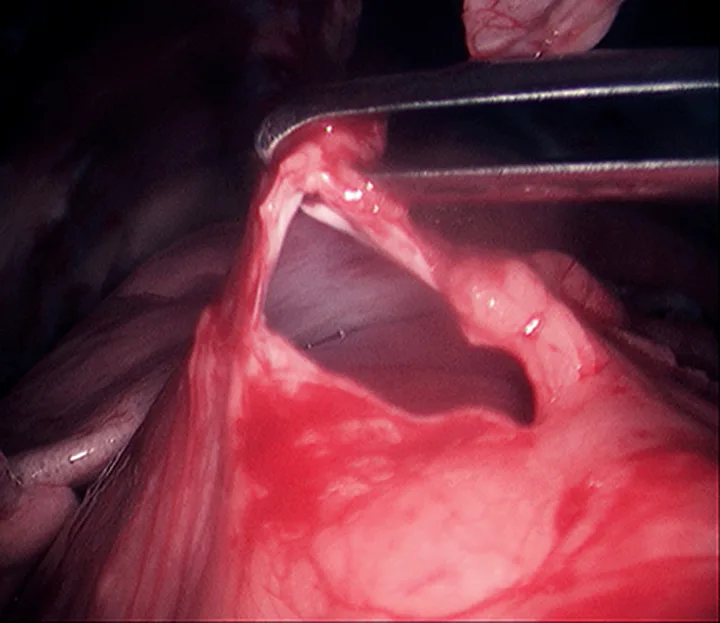

FIGURE 3

10-mm Babcock forceps grasping the pyloric antrum during a laparoscopic-assisted gastropexy (A) and completed gastropexy with the pyloric antrum (black arrow) sutured to the right lateral abdominal wall (B; white arrow)

After placement of the 2 ports and insufflation of the abdomen, with the patient in dorsal recumbency, the pyloric antrum is grasped midway between the greater and lesser curvature (Figure 3A), and the antrum is elevated to the right lateral abdominal wall. The length of the paracostal port incision is enlarged. The pyloric antrum is exteriorized, and 2 stay sutures are placed at the oral and aboral extents of the proposed gastropexy site to stabilize the stomach and maintain exposure. An incision is then made in the pyloric antrum, similar in location to that made for a conventional incisional gastropexy. Each edge of the seromuscular incision of the stomach is sutured to the transverse abdominus muscle in a simple continuous suture pattern using a slowly absorbing suture material. The internal and external abdominal oblique muscles are reapposed over the gastropexy site using a simple continuous pattern, followed by routine closure of subcutaneous tissue and skin. Once the abdominal wall is closed, insufflation is re-established and the gastropexy site is examined for proper positioning before routine closure of the camera port site (Figure 3B).